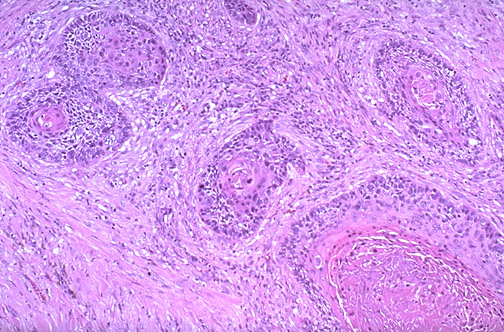

Image 3.4

By light microscopy the tissue from the mass displays cells in nests with

central keratin pearls

. There is an extensive fibrous stroma (desmoplasia).